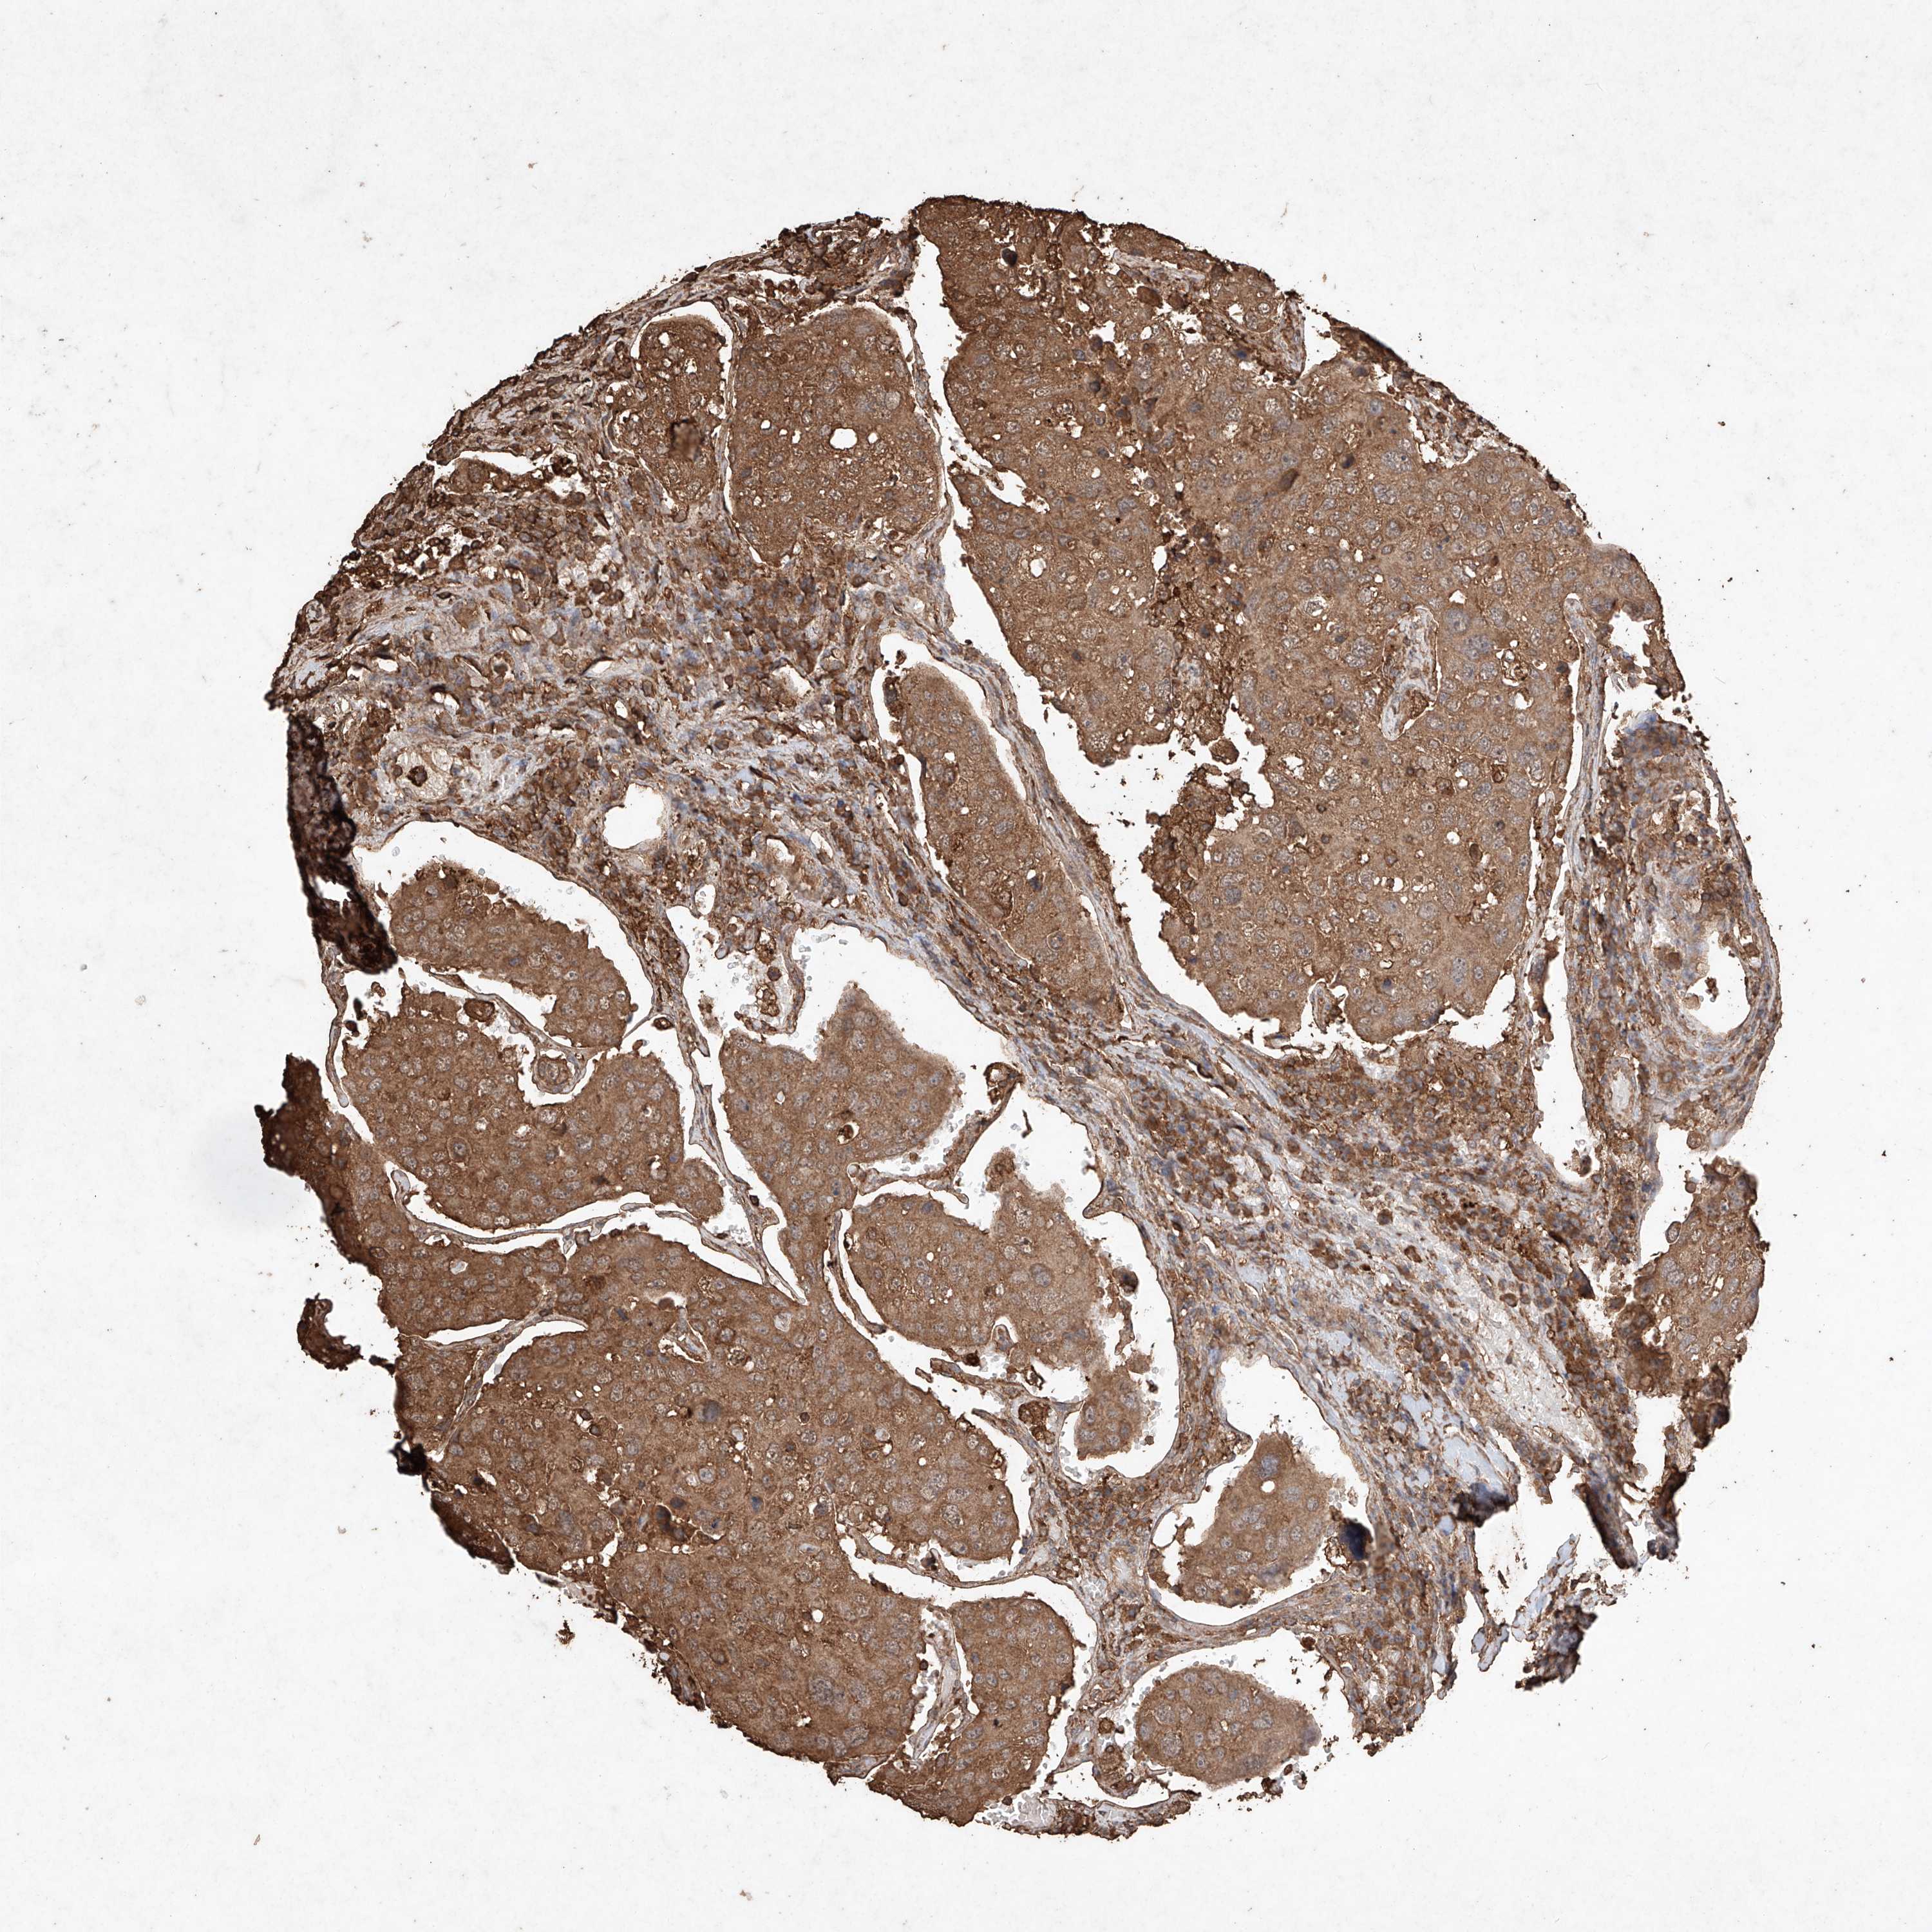

UROTHELIAL CANCER - Protein expressioni

A mouse-over function shows sample information and annotation data. Click on an image to view it in a full screen mode. Samples can be filtered based on level of antibody staining by selecting one or several of the following categories: high, medium, low and not detected. The assay and annotation is described here.

Note that samples used for immunohistochemistry by the Human Protein Atlas do not correspond to samples in the TCGA dataset.

Antibody stainingi

Antibody staining in the annotated cell types in the current human tissue is reported as not detected, low, medium, or high, based on conventional immunohistochemistry profiling in selected tissues. This score is based on the combination of the staining intensity and fraction of stained cells.

Each image is clickable and will lead to virtual microscopy that enables deeper exploration of all samples and also displays staining intensity scores, fraction scores and subcellular localization as well as patient and tissue information for each sample.

Antibody HPA040445

Antibody CAB034464

Urothelial carcinoma, High grade

Urothelial carcinoma, Low grade